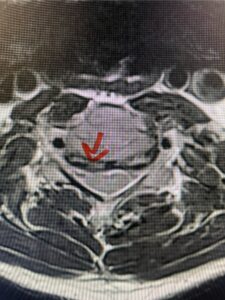

Another patient, a 77 year-old female, presents with pain, numbness, and weakness of her arms and difficulty with balance over a 6-month period. MRI revealed severe osteophytic disease at C5-C7 with cord compression (Fig. 4). Further work-up by fine-cut cervical CT to evaluate the nature of compression revealed a completely calcified osteophyte (Fig. 5). Although the patient had a good lordosis and a posterior cervical approach would accomplish an adequate decompression, we elected to perform a two-level anterior cervical discectomy and fusion. This particular osteophyte is formidable because of its size but the compression was all anterior and would be a less invasive approach. Fortunately, during the procedure, the patient had a fair amount of osteoporosis which allowed the osteophyte to be drilled and bit away with considerable ease. Interestingly, the C6 7 osteophyte which was more a sheet of osteophyte was more challenging to remove. In the end the decompression went well, and we placed two interbody devices filled with bone graft with plates at each level (Fig. 6). The patient had a nice recovery with immediate reduction of pain and numbness. This case demonstrates the importance of recognition of cervical myelopathy in its early stages. A significant reversal of function is generally the rule if the patient has appropriate correlative findings on exam and MRI, particularly with long tract distribution weakness development within a year time period.

Figs 4a: Sagittal and axial T2-weighted cervical MRIs demonstrating large osteophyte worse at C5-6 compressing spinal cord more eccentrically to the left (red arrows)

Fig 4b

Fig 4c

Fig 5a: Sagittal and axial cervical fine-cut CT scan demonstrating severe osteophyte formation causing cord compression at C 56 (red arrow)

Fig 5b: Sagittal and axial cervical fine-cut CT scan demonstrating severe osteophyte formation causing cord compression at C 56 (red arrow)

Fig 6: Intraoperative lateral cervical x-ray demonstrating placement of interbody cages and plates